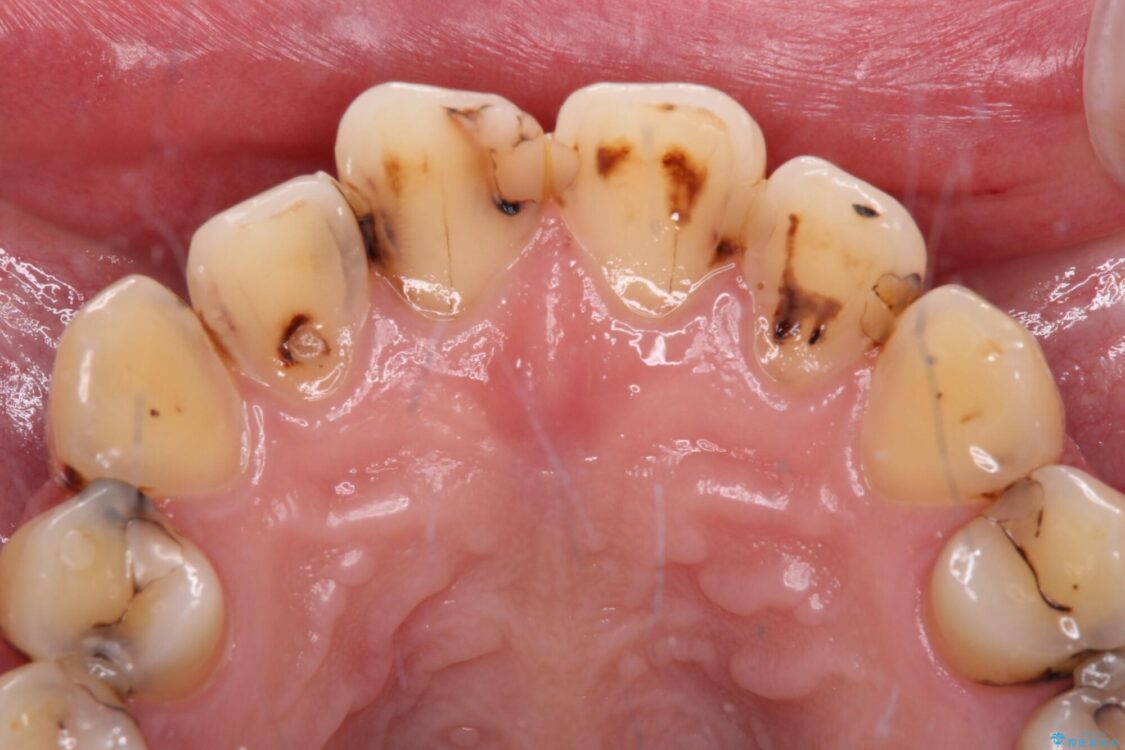

上下前歯や奥歯の虫歯治療を希望して来院された患者様です。

全顎的にむし歯が多く、根管治療の必要な奥歯や、審美的に気になっている前歯を中心にオールセラミッククラウンにて補綴治療を行うこととしました。

上顎前歯は歯肉退縮により歯根が露出していたため、事前に歯肉移植術により根面被覆を行い、その後にオールセラミッククラウンを装着することとしました。

治療前

• むし歯だらけの前歯をオールセラミッククラウンできれいに 治療前画像